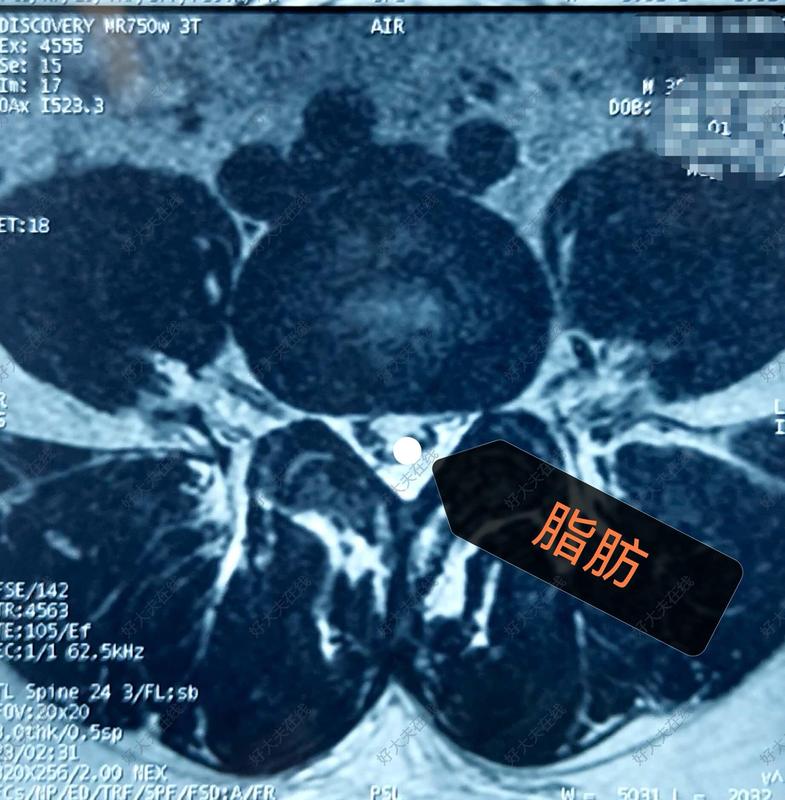

UBE技術(shù)corner區(qū)應(yīng)用解剖

Corner是一個重要的解剖區(qū)域,它是由下位椎體的椎板上緣與下位椎體的上關(guān)節(jié)突內(nèi)緣圍成的區(qū)域。其下方就是同側(cè)走行根,所以該區(qū)域是減壓手術(shù)的重點減壓位置。使用椎板咬骨鉗切除該區(qū)域部分骨質(zhì)可顯露出黃韌帶的遠端止點。向外側(cè)方向減壓可到達椎弓根內(nèi)壁,這也是同側(cè)減壓的外界。